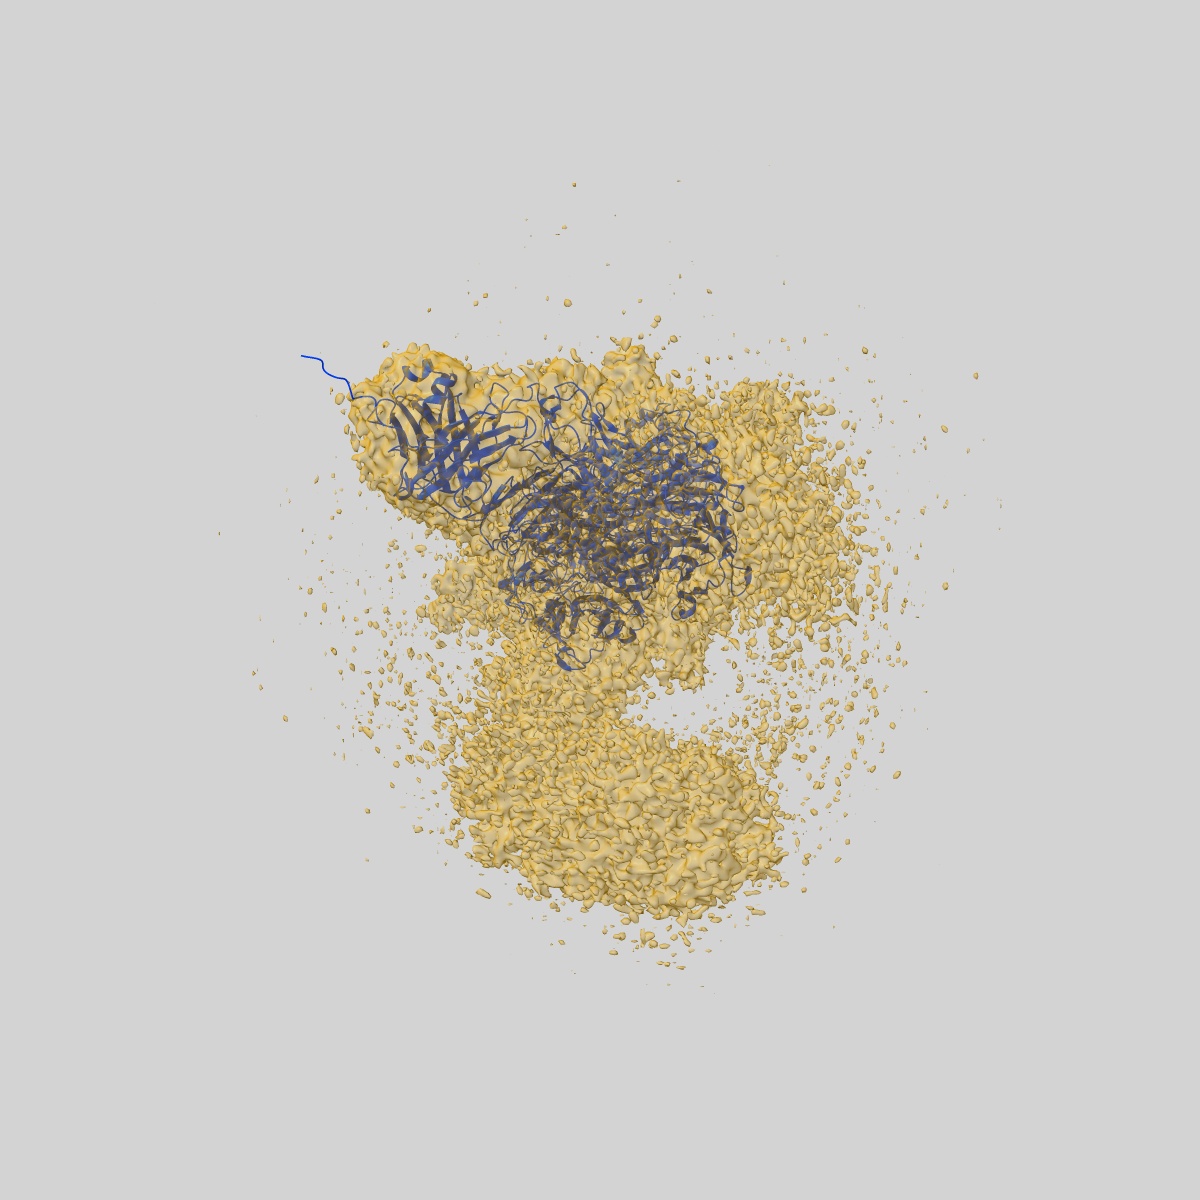

Cryo-EM structure of conformation 2 of complex of Nipah virus attachment G with 1E5 neutralizing antibody

Single-particle2.94 Å

Sample: Cryo-EM structure of conformation 2 of complex of Nipah virus attachment G with 1E5 neutralizing antibody

Fitted models: 8k0d

A potent Henipavirus cross-neutralizing antibody reveals a dynamic fusion-triggering pattern of the G-tetramer.

(2024) Nat Commun , 15 , 4330 - 4330